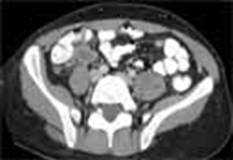

a) sectiune transversala (contrast în tubul digestiv)

a)

Explorarea tractului gastro-intestinal impune administrarea - orala sau prin clisma - de medii de contrast (bariu, substante iodate sau apa) în cursul procedurii pentru a creste vizibilitatea anumitor structuri tisulare.